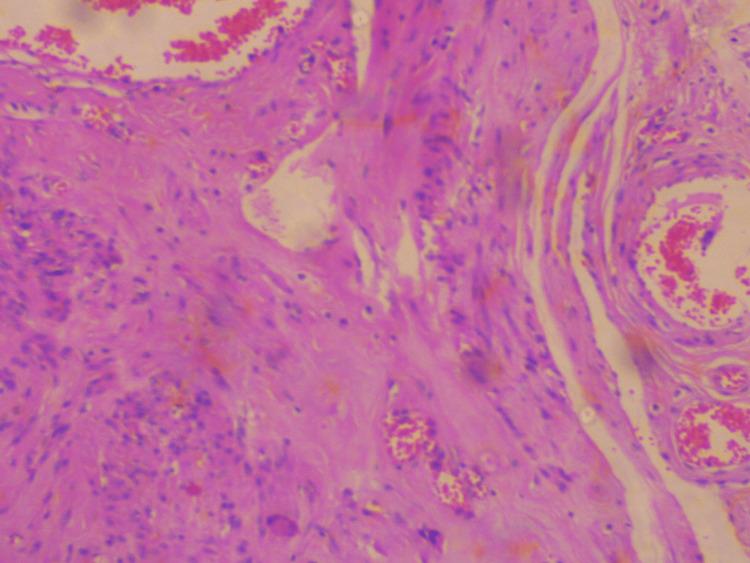

Large extra cervical-type posterior subserosal leiomyomas originating from the cervix are extremely rare. Our case concerns the surgical treatment of a large posterior pedunculated subserosal extracervical leiomyoma of the uterus with extension to the retroperitoneal space, which was associated with chronic low back pain. A 45-year-old patient, without menstrual disorders and with a medical history of chronic low back pain with sciatica, was referred for gynecological evaluation. The gynecological examination revealed the presence of a large pelvic mass, which occupied the pouch of Douglas. Preoperative imaging confirmed the presence of a solid pelvic mass, but its origin could not be clarified. Neither transvaginal ultrasound nor MRI could establish the diagnosis of extracervical leiomyoma of the uterus. Based on the clinical and imaging findings, surgical management of the patient was decided with laparotomy. Intraoperatively, a large extracervical pedunculated leiomyoma was found, which originated from the posterior wall of the cervix and extended into the retroperitoneal space. An abdominal total hysterectomy and bilateral salpingo-oophorectomy were performed. The procedure had significant surgical difficulties. The postoperative course was uneventful. Three months after surgery, the patient reported relief of symptoms. This paper highlights a brief review of cervical leiomyomas, highlighting the important difficulties regarding the preoperative diagnosis and surgical management of these patients.

源自宫颈的巨大宫颈外型浆膜下后位平滑肌瘤极为罕见。我们的病例涉及一例子宫浆膜下后位带蒂巨大宫颈外平滑肌瘤的手术治疗,该肌瘤延伸至腹膜后间隙,并伴有慢性腰痛。一名45岁患者,无月经紊乱,有慢性腰痛伴坐骨神经痛病史,前来接受妇科评估。妇科检查发现盆腔有一巨大肿块,占据了Douglas陷凹。术前影像学检查证实盆腔有一实性肿块,但其起源无法明确。经阴道超声和MRI均无法确诊子宫宫颈外平滑肌瘤。根据临床和影像学检查结果,决定对患者行剖腹手术治疗。术中发现一个巨大的宫颈外带蒂平滑肌瘤,起源于宫颈后壁并延伸至腹膜后间隙。行腹式全子宫切除术和双侧输卵管卵巢切除术。该手术有显著的手术难度。术后恢复顺利。术后三个月,患者报告症状缓解。本文简要回顾了宫颈平滑肌瘤,强调了这些患者术前诊断和手术治疗方面的重要难点。